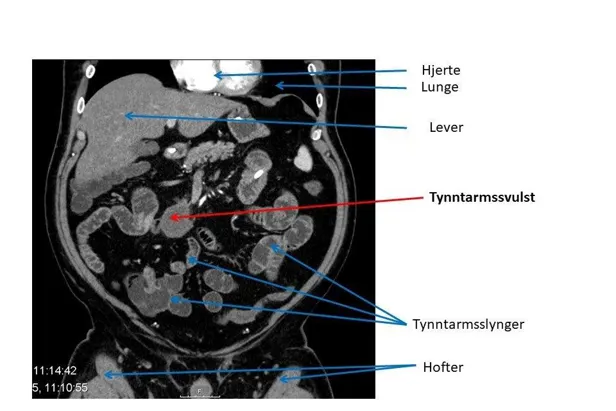

Ved hjelp av disse undersøkelsene kan en svulst påvises. Noen ganger kan imidlertid svulstene være såpass små, eller ligge slik til, at de ikke identifiseres på røntgenundersøkelsene. Ofte må det brukes kontrast på CT undersøkelsene for at svulsten skal oppdages (intravenøs kontrast i arteriell og portovenøs fase).

Likeledes vil MR-oppdage flere svulster og gi bedre tolkningsmuligheter av sykelige forandringer ved bruk av kontrast. MR er bedre til å påvise svulster i skjelettet enn CT.